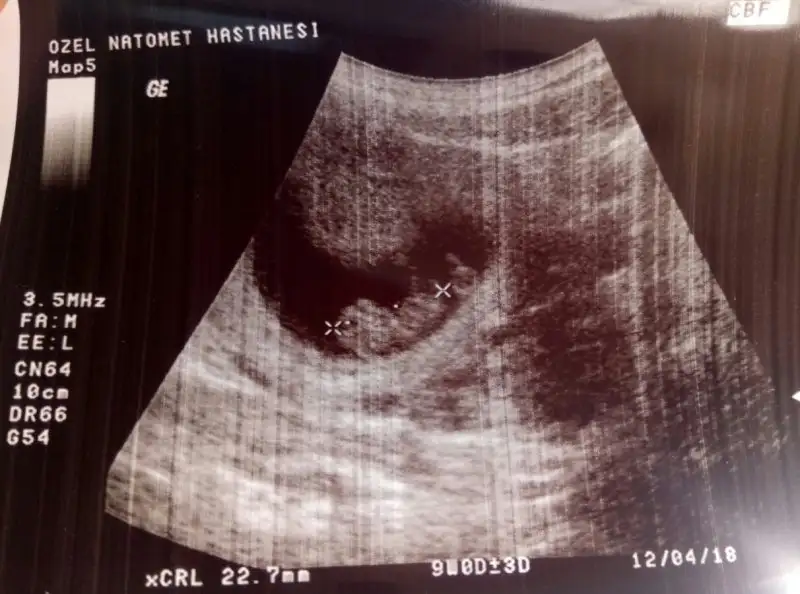

merhaba arkadaşlar benim görüntüde solda duruyor kap atışının olduğu yeri doktor işaretlemişti

merhabalar arkadaşlar 12 hafta 6 günlük olduk cinsiyet söylemedi doktorumuz 16. haftada dedi tahmni olan var mı?